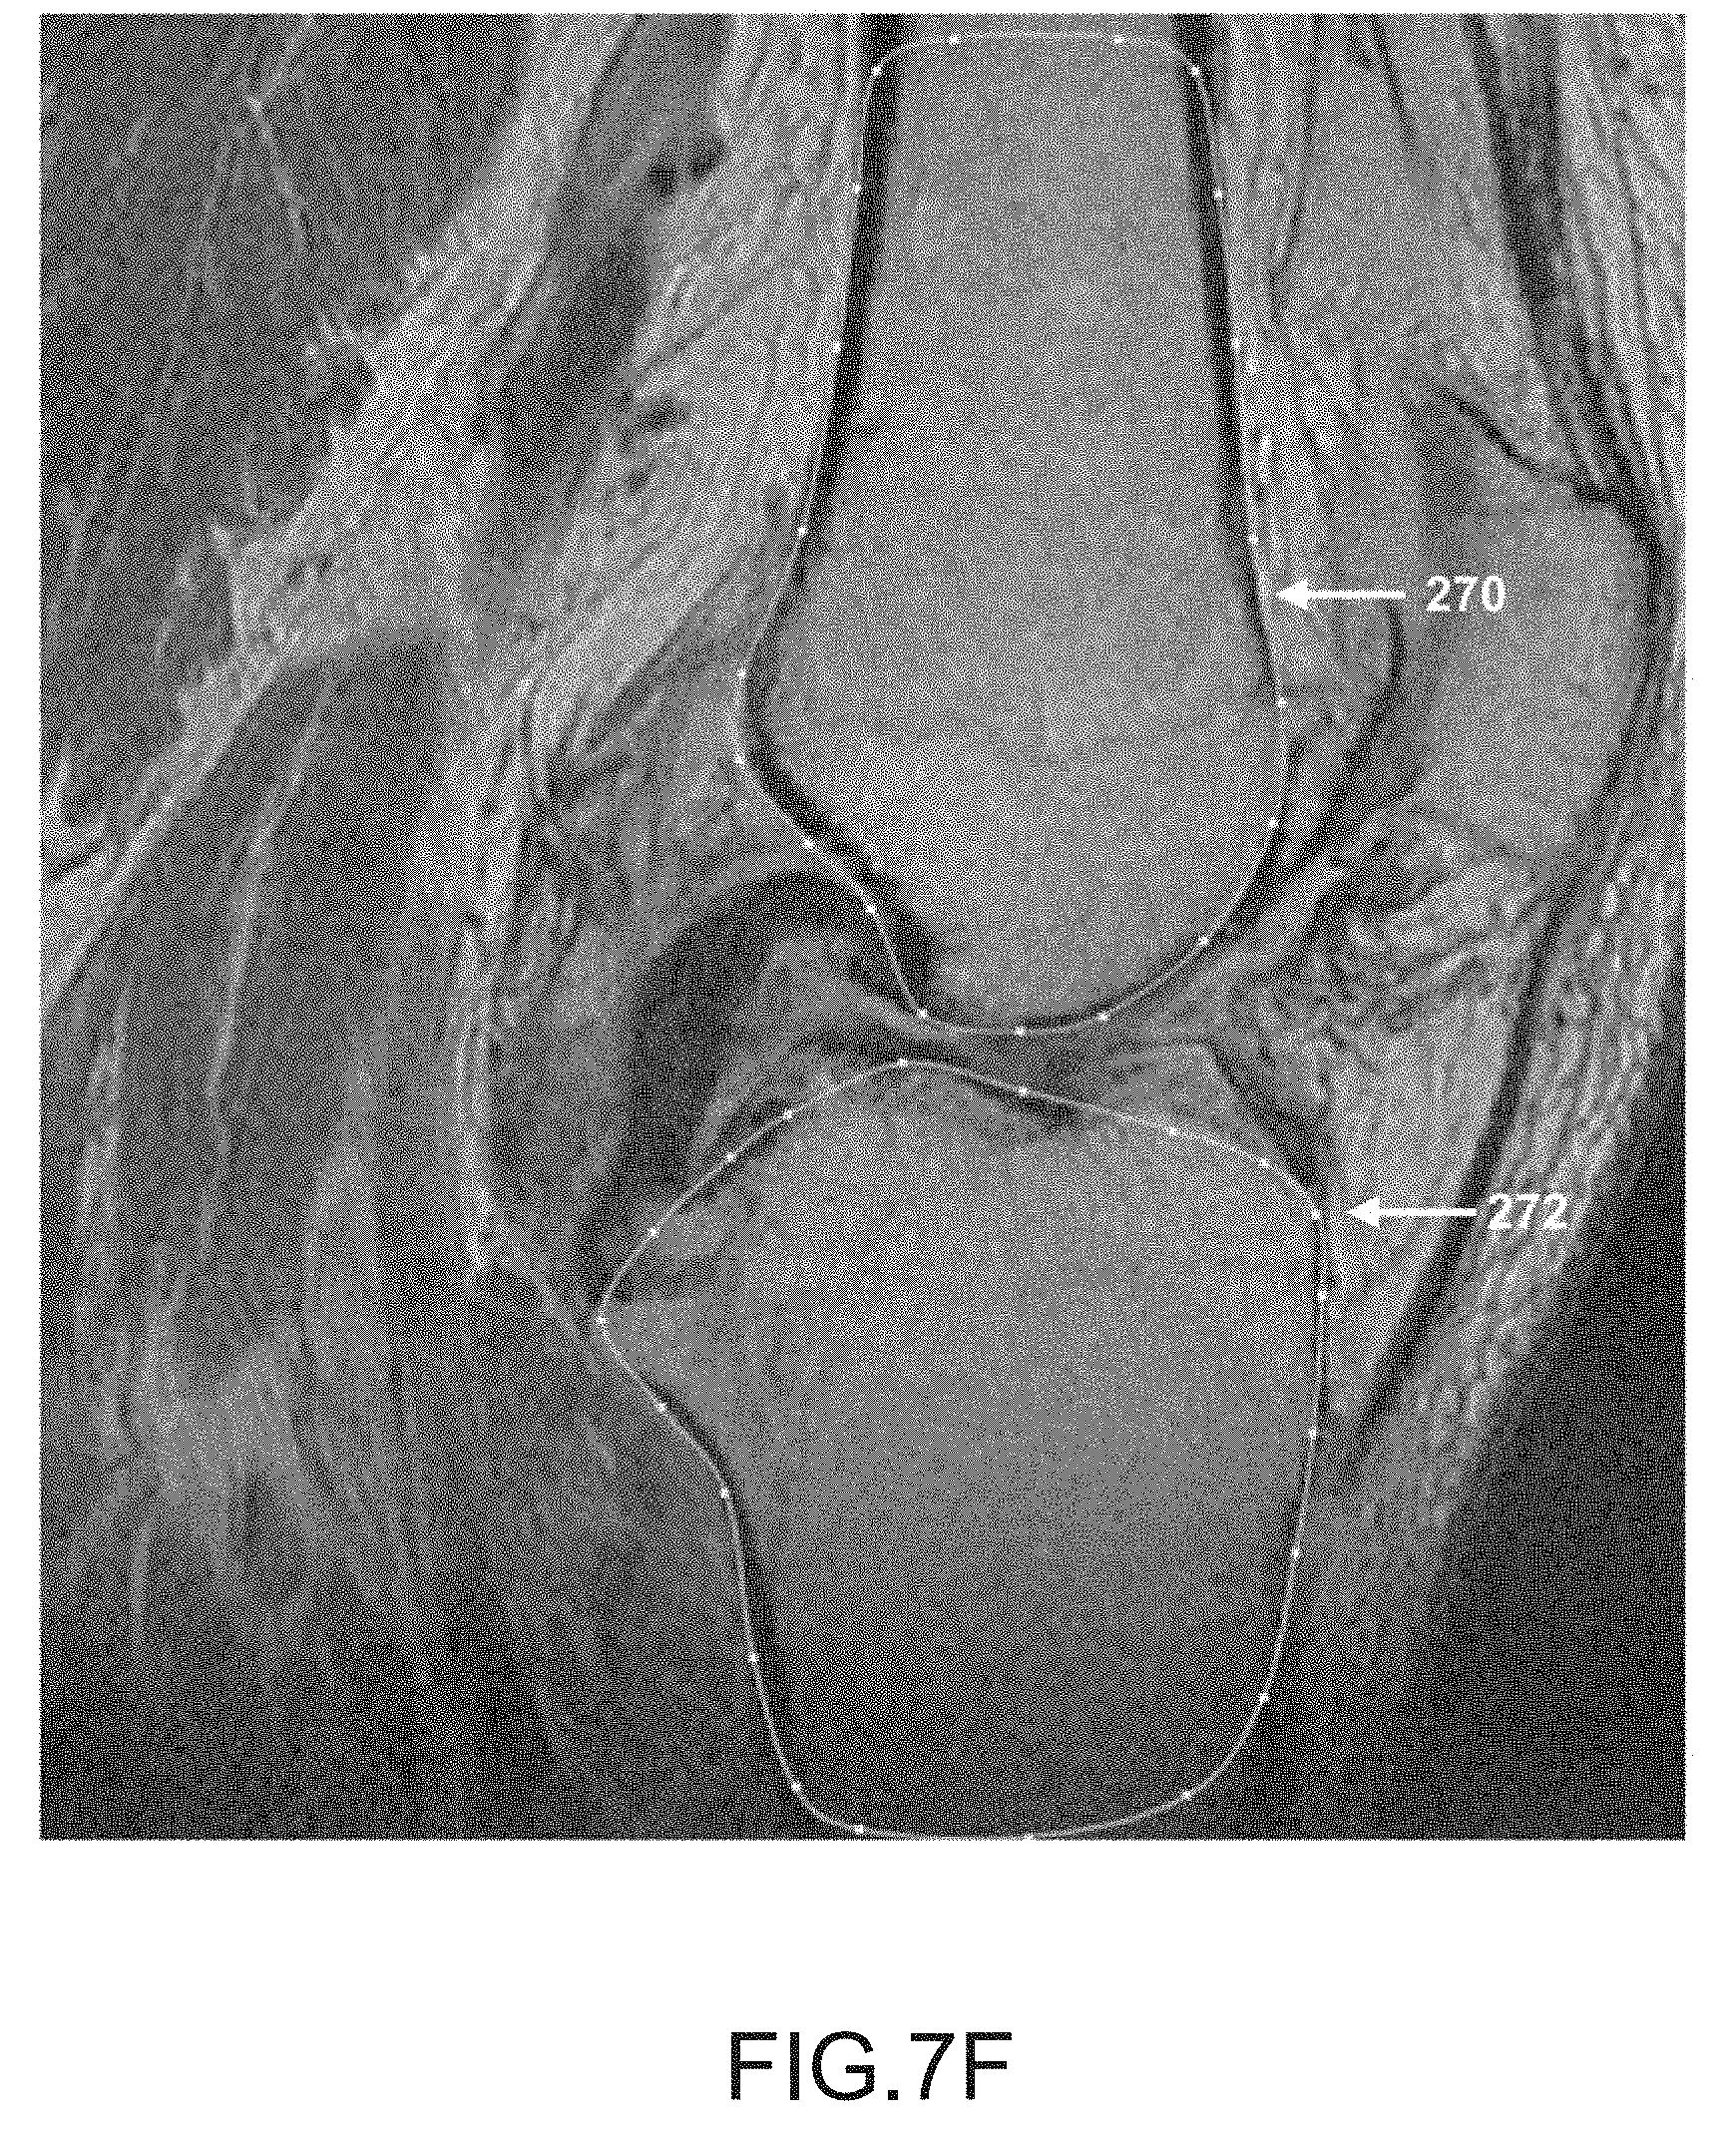

FIG. 7F is another sagittal plane image slice of a segmented femur and tibia.

[0162]

After operation 250 obtains scan data (e.g., scan images 16) generated by imager 8, operation 252 may be performed to segment the femur data of the scan data. During this operation, the femur may be located and spline curves 270 may be generated to outline the femur shape or contour lines in the scan slices, as depicted in FIGS. 7A-7K. It should be appreciated that one or more spline curves may be generated in each slice to outline the femur contour depending on the shape and curvature of the femur as well as the femur orientation relative to the slice direction.

[0165]

After operation 256, operation 258 may be performed to segment the tibia data in the scan data. During this operation, the tibia is located and spline curves may be generated to locate and outline the shape of the tibia found in the scan slices, as depicted by tibia spline curves 272 in FIGS. 7A-7K. It should be appreciated that one or more spline curves may be generated in each slice to outline the tibia depending on the shape and curvature of the tibia as well as the tibia orientation relative to the slice direction.